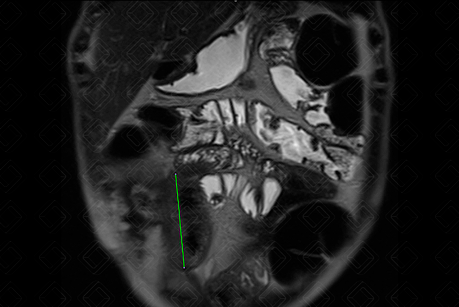

Texto alternativo para a imagem Figura 1. Créditos: Dra. Elazir Mota - Rio de Janeiro/RJ

Descrição da figura 1: EnteroRM sequência Haste (ponderada em T2), evidenciando espessamento parietal adjacente à anastomose ileocolônica, com extensão de cerca de 6,6 cm (seta verde). Neste caso, trata-se de paciente portadora de doença de Crohn com inúmeras manipulações cirúrgicas prévias, apresentando novo quadro de suboclusão.